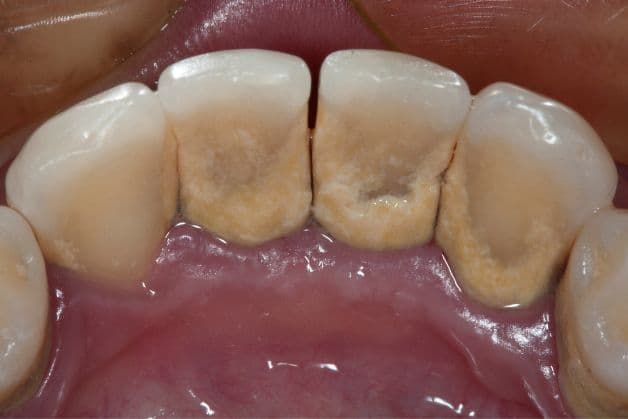

Mảng bám cao răng ở mặt sau của răng.

– Vôi răng thông thường có màu vàng nhạt, các mảng bám không quá dày

– Cao răng huyết thanh có màu nâu đỏ, nâu đen, ảnh hưởng thẩm mỹ nặng nề hơn

Vôi răng huyết thanh là hậu quả của việc không vệ sinh và loại bỏ vôi răng thông thường. Vi khuẩn tích tụ khiến lợi bị yếu đi, dễ chảy máu trong quá trình vệ sinh răng miệng. Vi khuẩn tích tụ nhiều hơn vôi răng thông thường làm gia tăng nguy cơ viêm nhiễm và mắc các bệnh răng miệng khác phức tạp hơn. Vì vậy, cần đến gặp bác sĩ, nha sĩ để loại bỏ cao răng ngay từ khi mới hình thành, tránh để tiến triển nặng hơn.